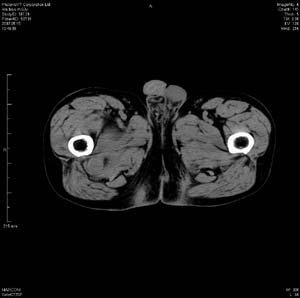

男 63岁 右大腿无痛性肿块11年,x片右大腿软组织肿块影,余无明显异常.ct值-13__239hu

右大腿股内侧股与收肌间隙间多发囊实性占位,界清.内示斑点状钙化.局部骨质无异常.肌肉推压移位表现.

考虑肌间隙病变.可有1,神经来源肿瘤.2,血管来源病变.3,淋巴来源肿瘤.4,脂肪来源肿瘤.5,滑膜来源肿瘤.结合病史只能考虑良性占位.建议增强或mri进一步分析.

同意,病史较长,病变周围分界清晰,考虑良性病变。病灶内有多发斑点状钙化,沿肌间隙生长,血管瘤或淋巴管瘤首先考虑。